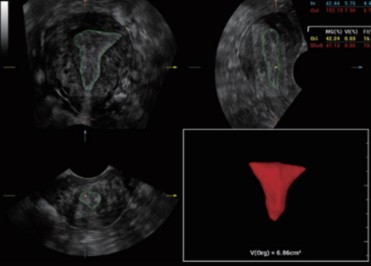

Ефективно открива анатомични структури с дори слаби граници като ендометриум. В допълнение, той предоставя цялостна оценка на съдовия отпечатък и интензитета на кръвния поток в целевата област, за да представи повече диагностична информация за възприемчивостта на ендометриума и разпределението на туморния кръвен поток.